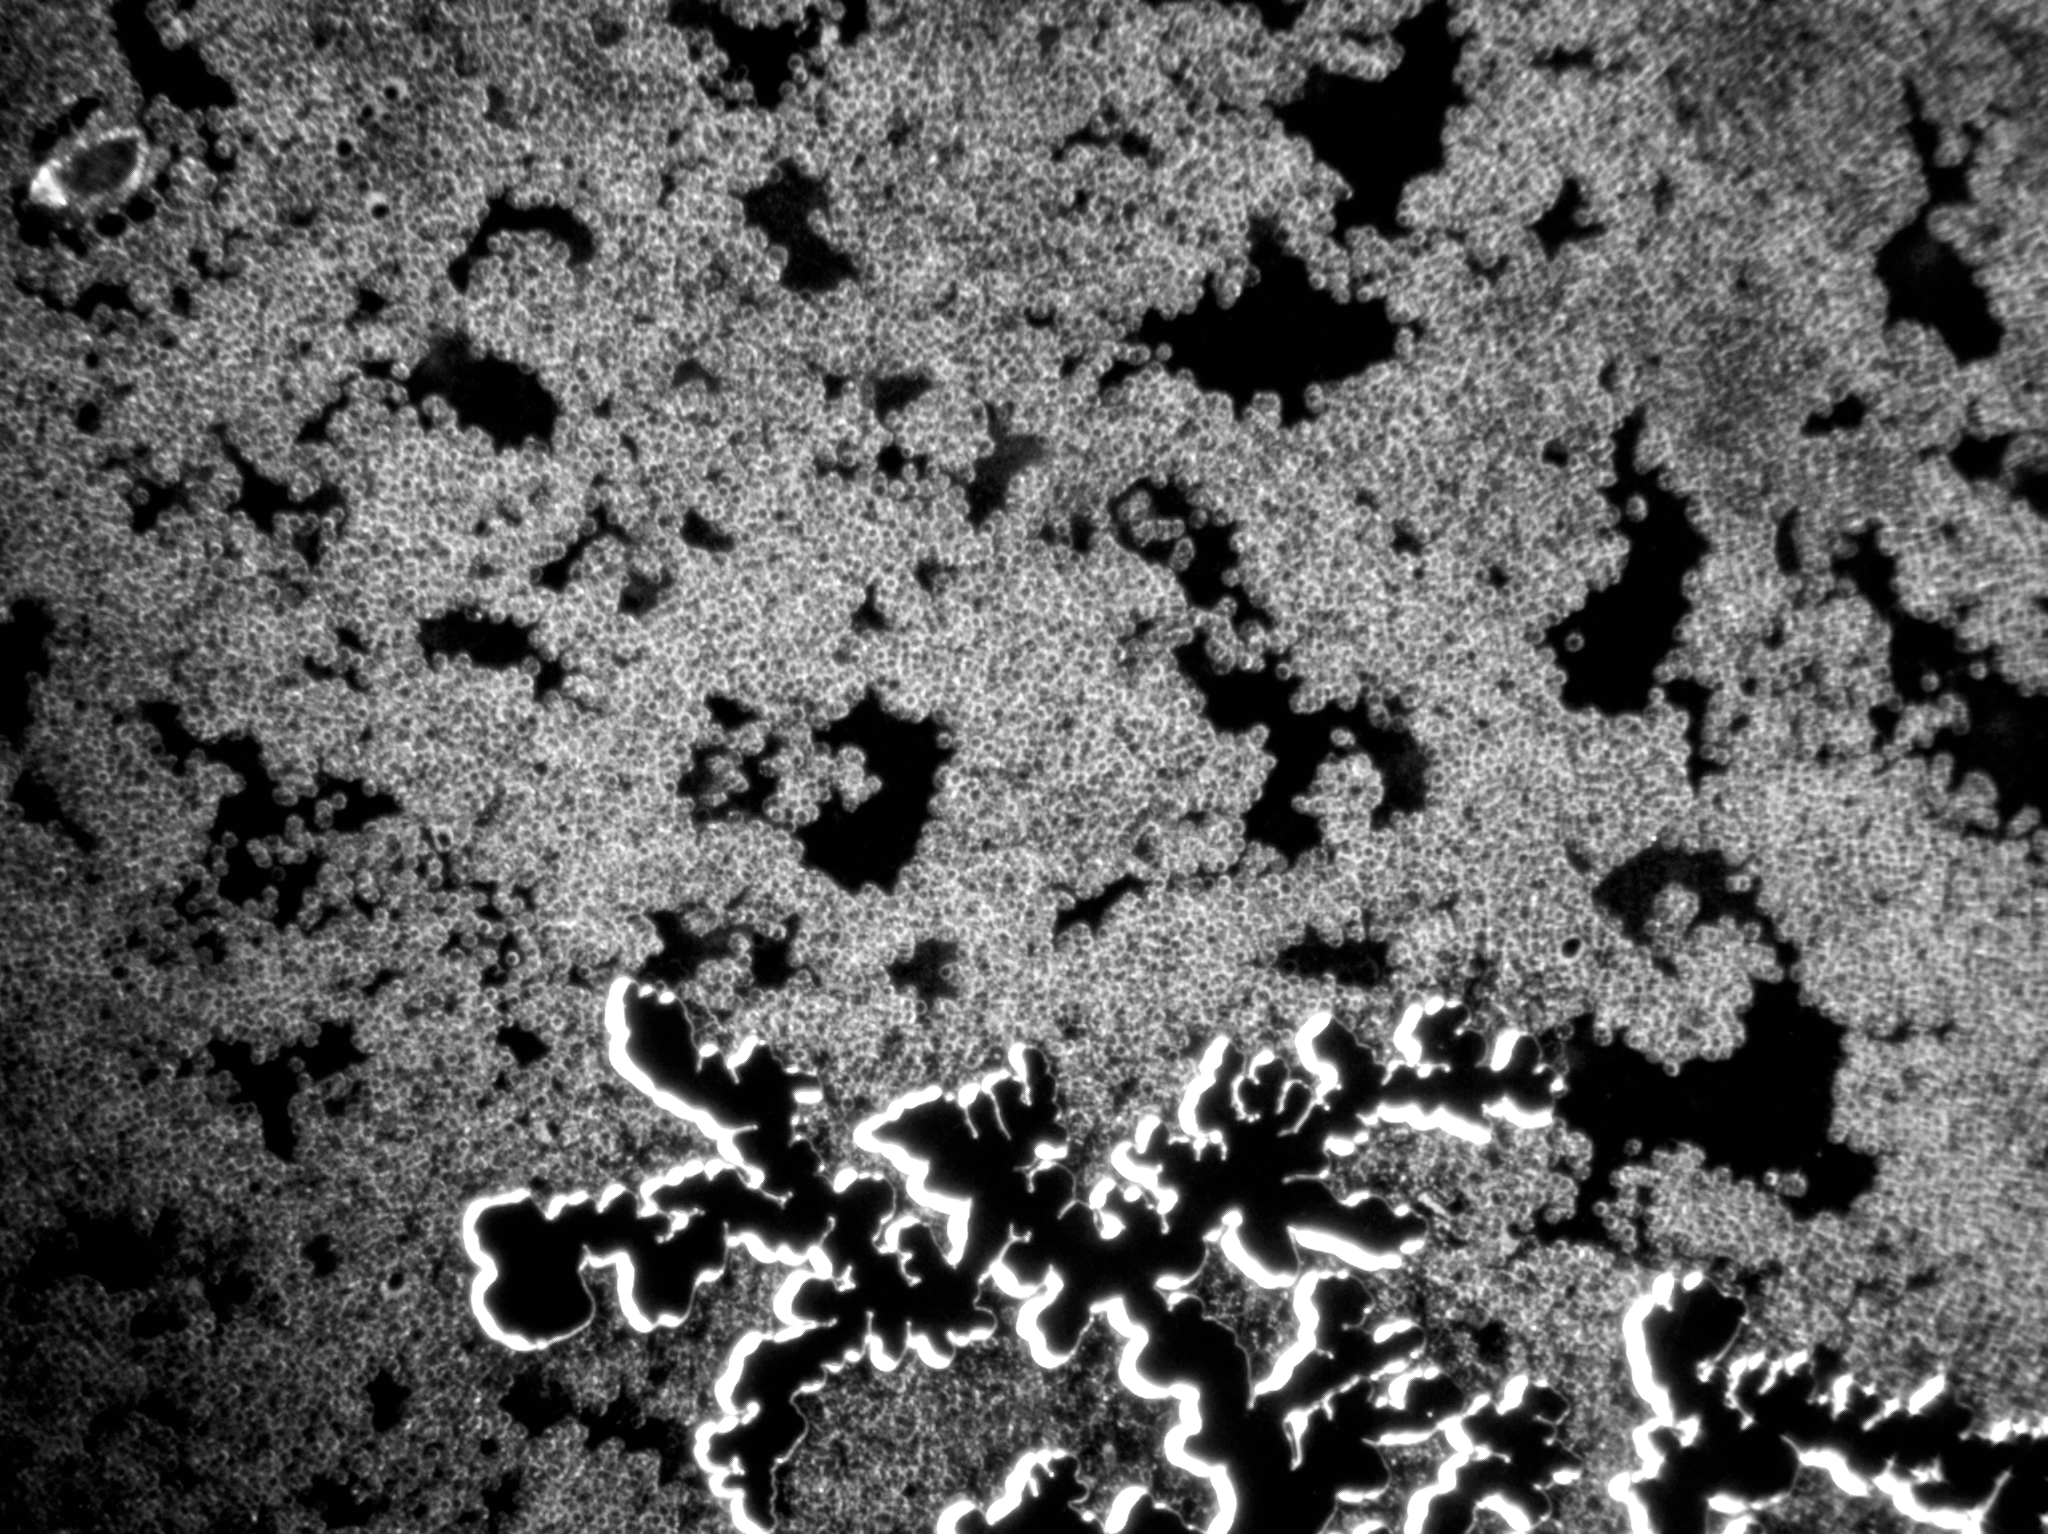

Vitalblutanalyse 1. Tag

Zeigt zahlreiche kreisförmige Strukturen (Erythrozyten) mit variierender Intensität. Einige Zellen scheinen aggregiert, andere einzeln verteilt. Weitfeld-Okulare mit 10-facher Vergrößerung & 40x Objektiv

Vitalblutanalyse 4. Tag

Offenbart ein dichtes Netzwerk mit unregelmäßigen, verzweigten Strukturen, möglicherweise Fibrin oder Zelltrümmer. Weniger erkennbare Zellen, könnte auf eine Entzündungsreaktion oder Gewebsschädigung hinweisen. Weitfeld-Okulare mit 10-facher Vergrößerung & 10x Objektiv